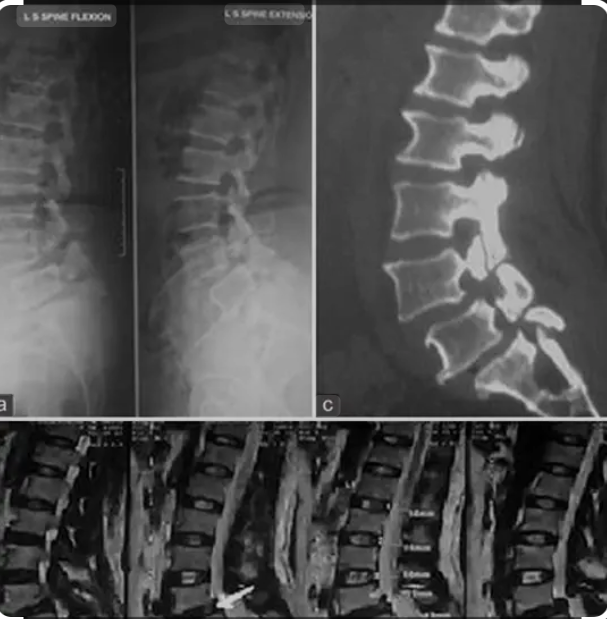

Medifyhome is providing X-ray Lumbosacral Spine AP/LAT/Extension/Flexion at an affordable price. An X-ray Lumbosacral Spine AP/LAT/Extension/Flexion is a series of imaging tests used to evaluate the structure, alignment, and movement of the lumbosacral spine (lower back and sacrum). The AP (Anterior-Posterior) view provides a front-to-back perspective, assessing alignment, disc spaces, and bony structures, while the LAT (Lateral) view offers a side view to evaluate spinal curvature, disc height, and vertebral alignment. The Extension/Flexion views are dynamic images taken while the patient bends backward (extension) and forward (flexion) to assess spinal mobility and detect instability.

During the procedure, the patient stands or lies down in specific positions for the AP and LAT views and performs bending movements for the extension/flexion views. While the X-ray provides valuable information, it has limitations, such as limited soft tissue detail compared to MRI or CT and minimal radiation exposure. Overall, it is a non-invasive, cost-effective tool for diagnosing and monitoring lower back conditions. To book an X-ray Lumbosacral Spine AP/LAT/Extension/Flexion with Medifyhome, visit our website or call us at +919100907036 or +919100907622. Experience hassle-free, reliable, and affordable medical imaging services tailored to your needs. Trust Medifyhome for accurate diagnostics and a seamless healthcare experience.

The X-ray Lumbosacral Spine AP (Anteroposterior), LAT (Lateral), Extension, and Flexion Views are radiographic imaging techniques used to assess the lumbosacral region, which includes the lumbar vertebrae (L1-L5) and sacrum. These X-rays help evaluate spinal alignment, detect fractures, assess degenerative changes, and identify conditions such as spondylosis, disc herniation, scoliosis, instability, or infections.